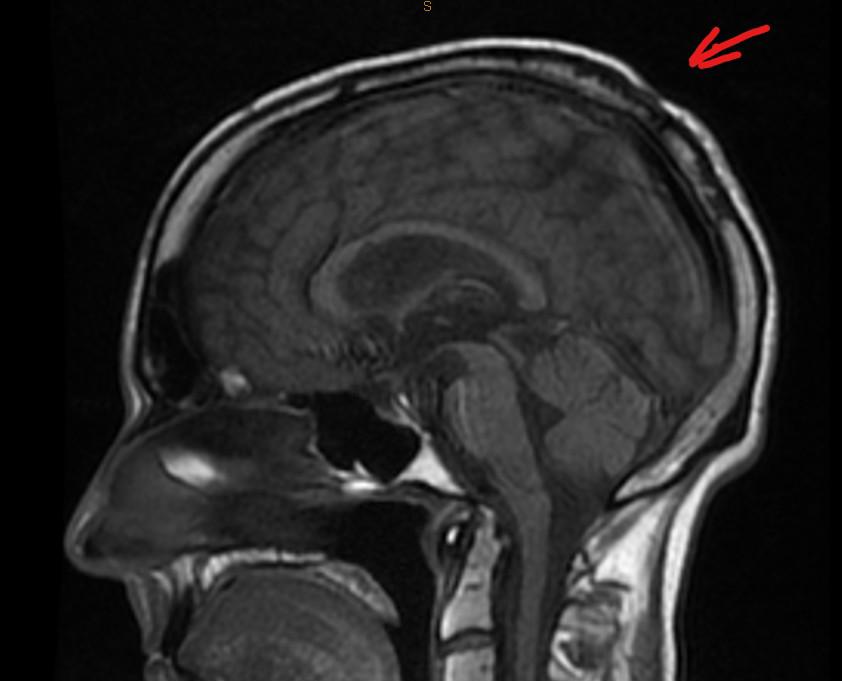

In parting, I came across one of my MRI scans. I can remember what I did to the back of my skull, but it probably hurt.